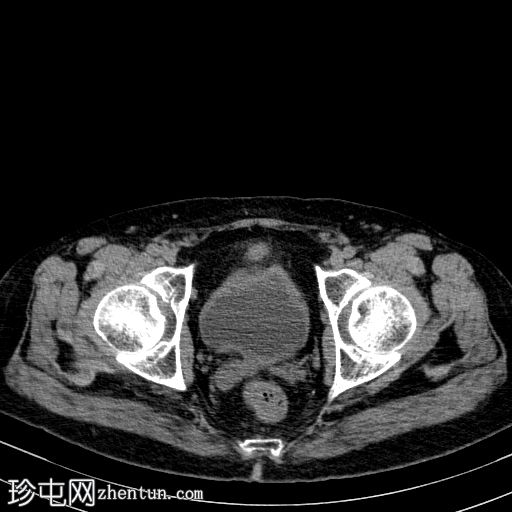

轴向

非造影

胰体尾弥漫性增大,特征为胰腺实质低强化,无明显坏死区域。

该病灶与以下表现相关:

胰周筋膜平面边界不清的污迹,无明显壁形成、气室、固体碎片或血液产物。

病变范围如下:

病变横向延伸至左前肾旁间隙,伴有Gerota筋膜增厚。

病变向下延伸至盆腔。

无肠系膜或脾脏血管阻塞的证据。

未见导管扩张或钙化。